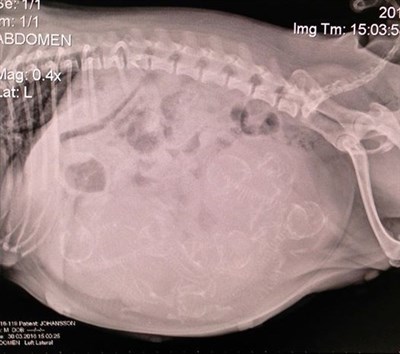

...vi har gjort en röntgen för att se hur många små som skall komma ut, det är ju alltid bra att veta, tycker jag iallafall.

Känns skönt att veta så slipper man fundera ! & det visade sig att det var ett helt gäng därinne

så spännande !!! men vi får hålla tummar och tassar att allt kommer gå smidigt och bra